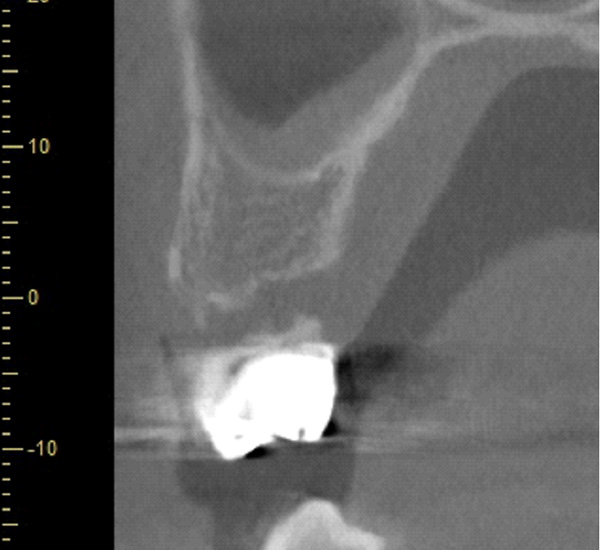

| 年代・性別 | 50代 男性 |

|---|---|

| 主訴 | 右上下の歯が痛い |

| 治療期間 | 約12ヶ月 |

| 費用 | 2,500,000円 |

| 治療内容 | インプラント、骨造成、結合組織移植、セラミック修復 |

| 治療に伴うリスク | インプラント周囲炎 セラミックの破折、脱離 |